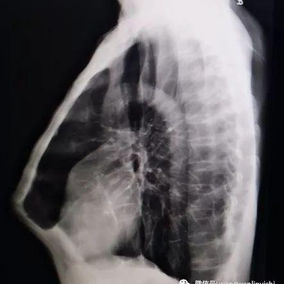

After a preoperative examination, it is observed that the patient's anterior chest wall protruded severely, reaching its peak at the xiphoid process, which presented as a 90-degree angle when viewed from the side. The heart is displaced to the right chest cavity, and the torso is severely deformed, characterized by a broad chest and a noticeably narrowed waist and abdominal area. The narrowing is most pronounced above the pelvis. Moreover, a chest CT scan reveals two large cysts located between the heart and the anterior chest wall in the lower lobe of the left lung, measuring 7x8 cm and 9x10 cm respectively.